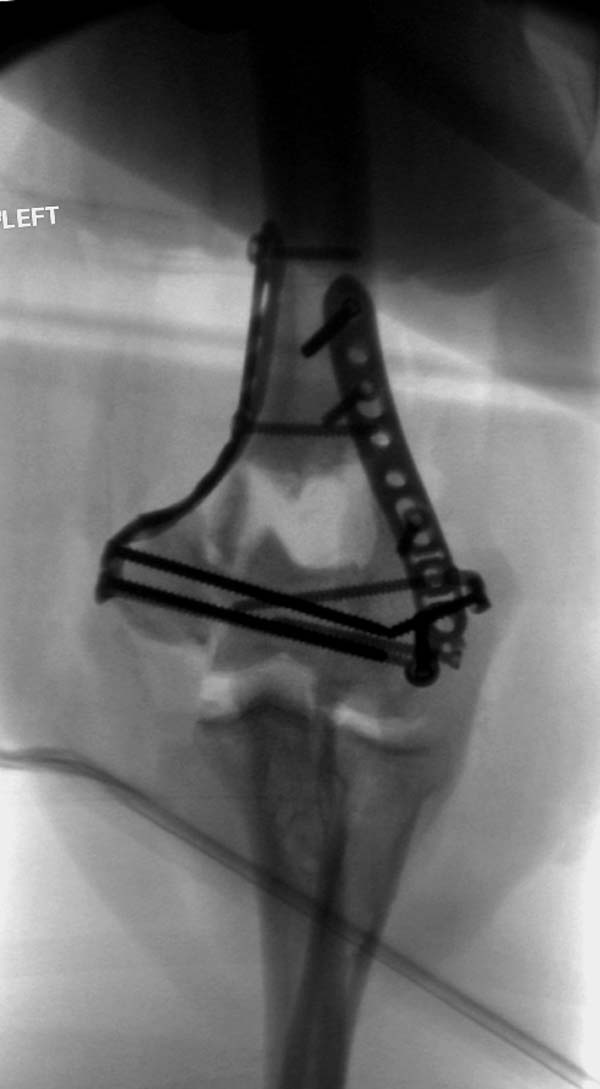

Примеры: первому более 15 лет фиксирован шурупом и tension band

technique, а второй перелом открытый больной 80 лет, после наружного

фиксатора в первом этапе и окончательная фиксация вторично. Третьий раз

внесуставная остеотомия...

Вложение не в текстовом формате было извлечено&hellip;

Имя     : 2-1 Distal Humerus.jpg

Тип     : image/jpeg

Размер  : 66695 байтов

Описание: отсутствует

Url     : http://weborto.net:8080/pipermail/ortho/attachments/20130604/c45a379f/attachment-0020.jpg